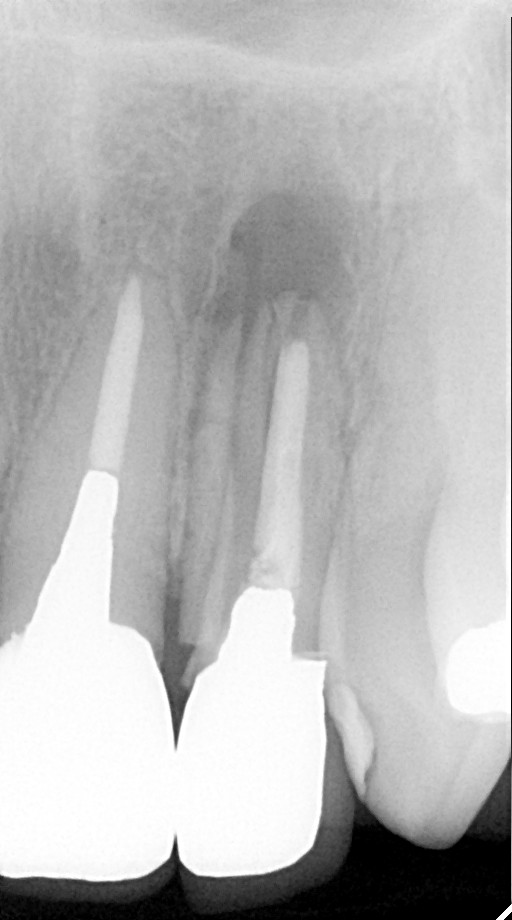

インプラント治療の症例紹介②

Before

After

主訴

前歯の脱落、歯肉の腫れ

治療内容

修復物の脱落時に支台築造のポスト部で歯質を破折。抜歯即時インプラント埋入をおこなったケース。

治療費

473,000 円(税込)

治療期間

8か月

治療回数

12回

想定されたリスク

※経年的な歯肉退縮の恐れ、インプラント周囲炎の恐れがありました。

残存した歯根に感染が少なく、抜歯時即時にインプラント埋入手術を行った。術後〇年経過し安定している状態。